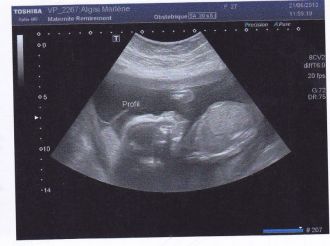

écho 3 eme trimestre

Voila c fait pour moi ce n'est pas la dernière à caused mon diabète j'en ai toutes les 2 semaines.

puce a toujours eu la tête en bas sur toutes les échos et la biensur on s'approche de la fin hop elle est en siège lol.. sinon tout va bien elle est bien dans les normes..

on a eu le droit a 2 fots 3d mais on ne voi pa tout son visage elle cache sa fente je vous met la plus belle si j'y arrive lol

Message déposé le 30.08.2013 à 20:41 - Commentaires (1)